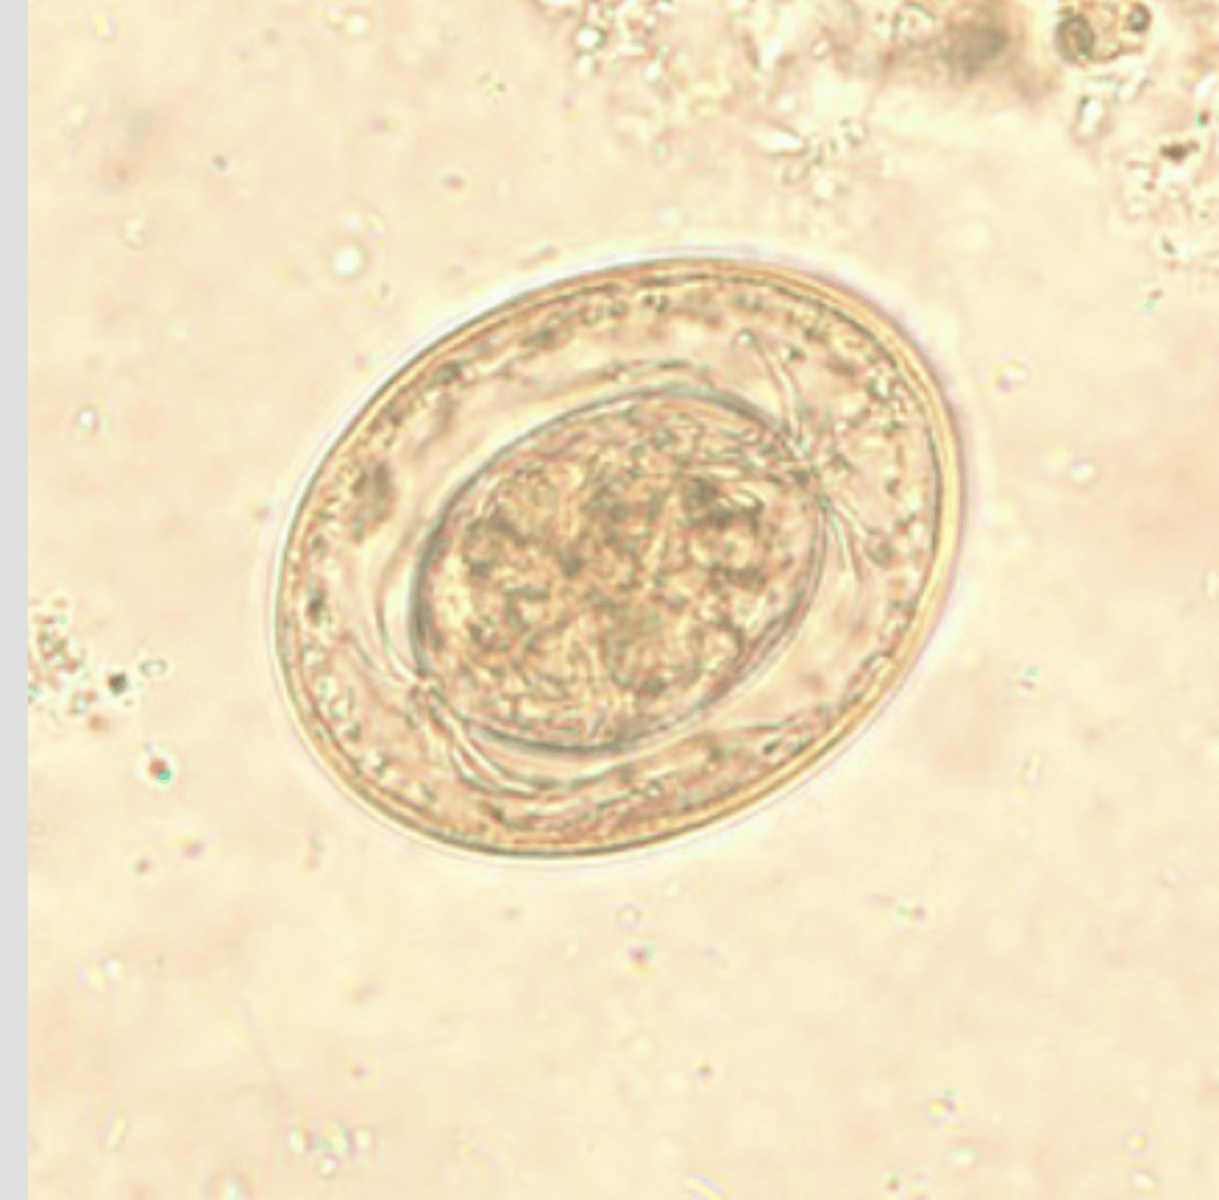

Taenia spp. egg